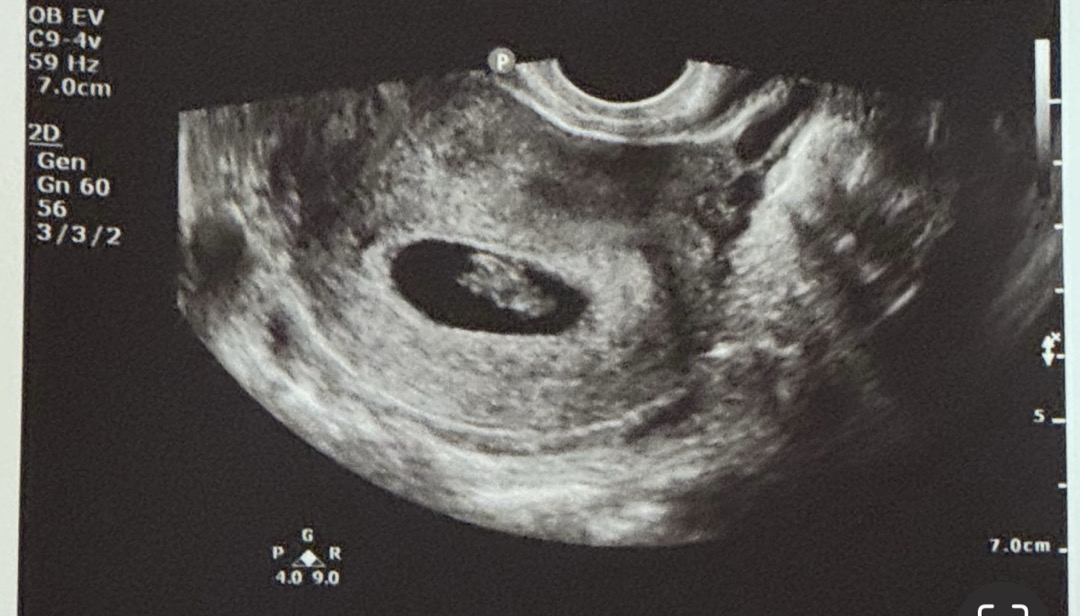

8주0일 초음파 봐주세요! 🥹

미국에서 초음파 했고 기준상 8주 0일인데 초음파오는 7주 5일정도로 보인다고 하더라고요! 이렇게 봐서는 아기 형태가 전혀 안보이는데.. 혹시 머리나 팔다리 보이시나요..? 심장박동은 들려주진 않았지만 165였습니다! 다음초음파가 12주차 예정이라 답답한 마음에 올려보아요

아직 사람모양은 아니에용 그래도 애기 너무 잘보여요^~^

이때쯤이면 생선모양(?)이 정상이라고 하셨어요 ㅋㅋ 제 산과 선생님은 팔다리 생긴 젤리곰은 9주쯤 보이고 7-8주는 그냥 길쭉한 생선같다고 하셨어요! 근데 그걸 너무 귀엽다고 표현하시더라구요 ㅎㅎ 머리와 몸통만 있는 태초의 상태라고 ㅎㅎㅎㅎ

아기 잘 보이는데요?ㅎㅎ 아직 명확하게 사람형태는 아닐거에요 ㅎㅎ 심장도 잘 뛰네용 ㅎㅎ